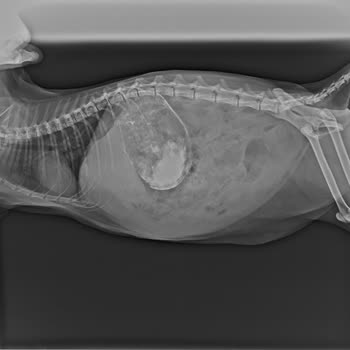

Arlen Veteriner Kliniği Zeytin Yanlış Teşhis Sonucu Vefat Etti

Arlen Veteriner Kliniği, Zeytin isimli evcil hayvanımızın hayatını kaybetmesine sebep oldu. Yanlış teşhis konularak 14 gün boyunca Zeytin'e yanlış tedavi uygulandı. 'Tıkanıklık olabilir mi?' diye sorduğumuzda ciddiye alınmadık. Israrlarımız sonucunda yapılan Doppler ultrasonu ile tıkanıklık tespit e...